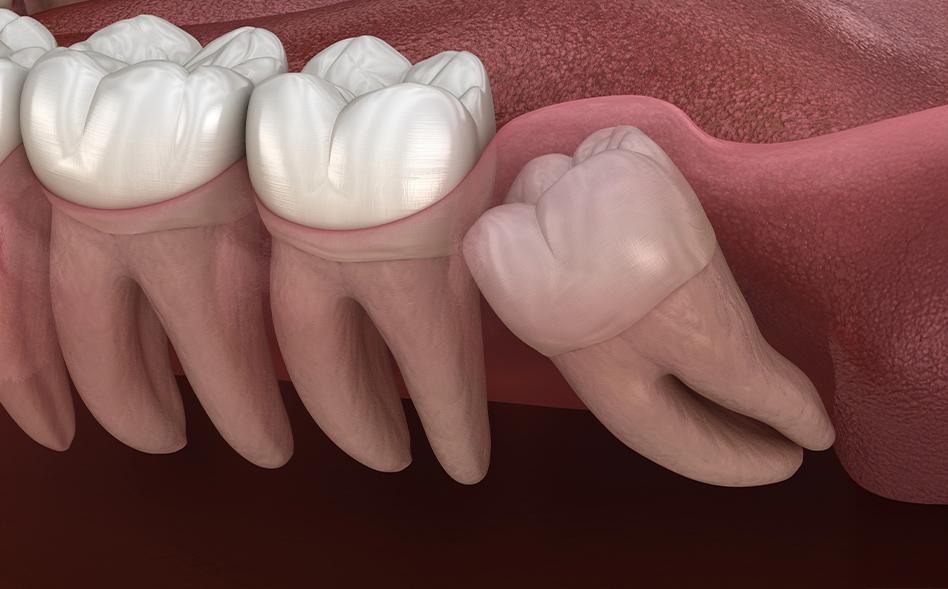

• Impaction – The tooth becomes trapped beneath the gum or jawbone

• Crowding – Limited space causes pressure on neighbouring teeth